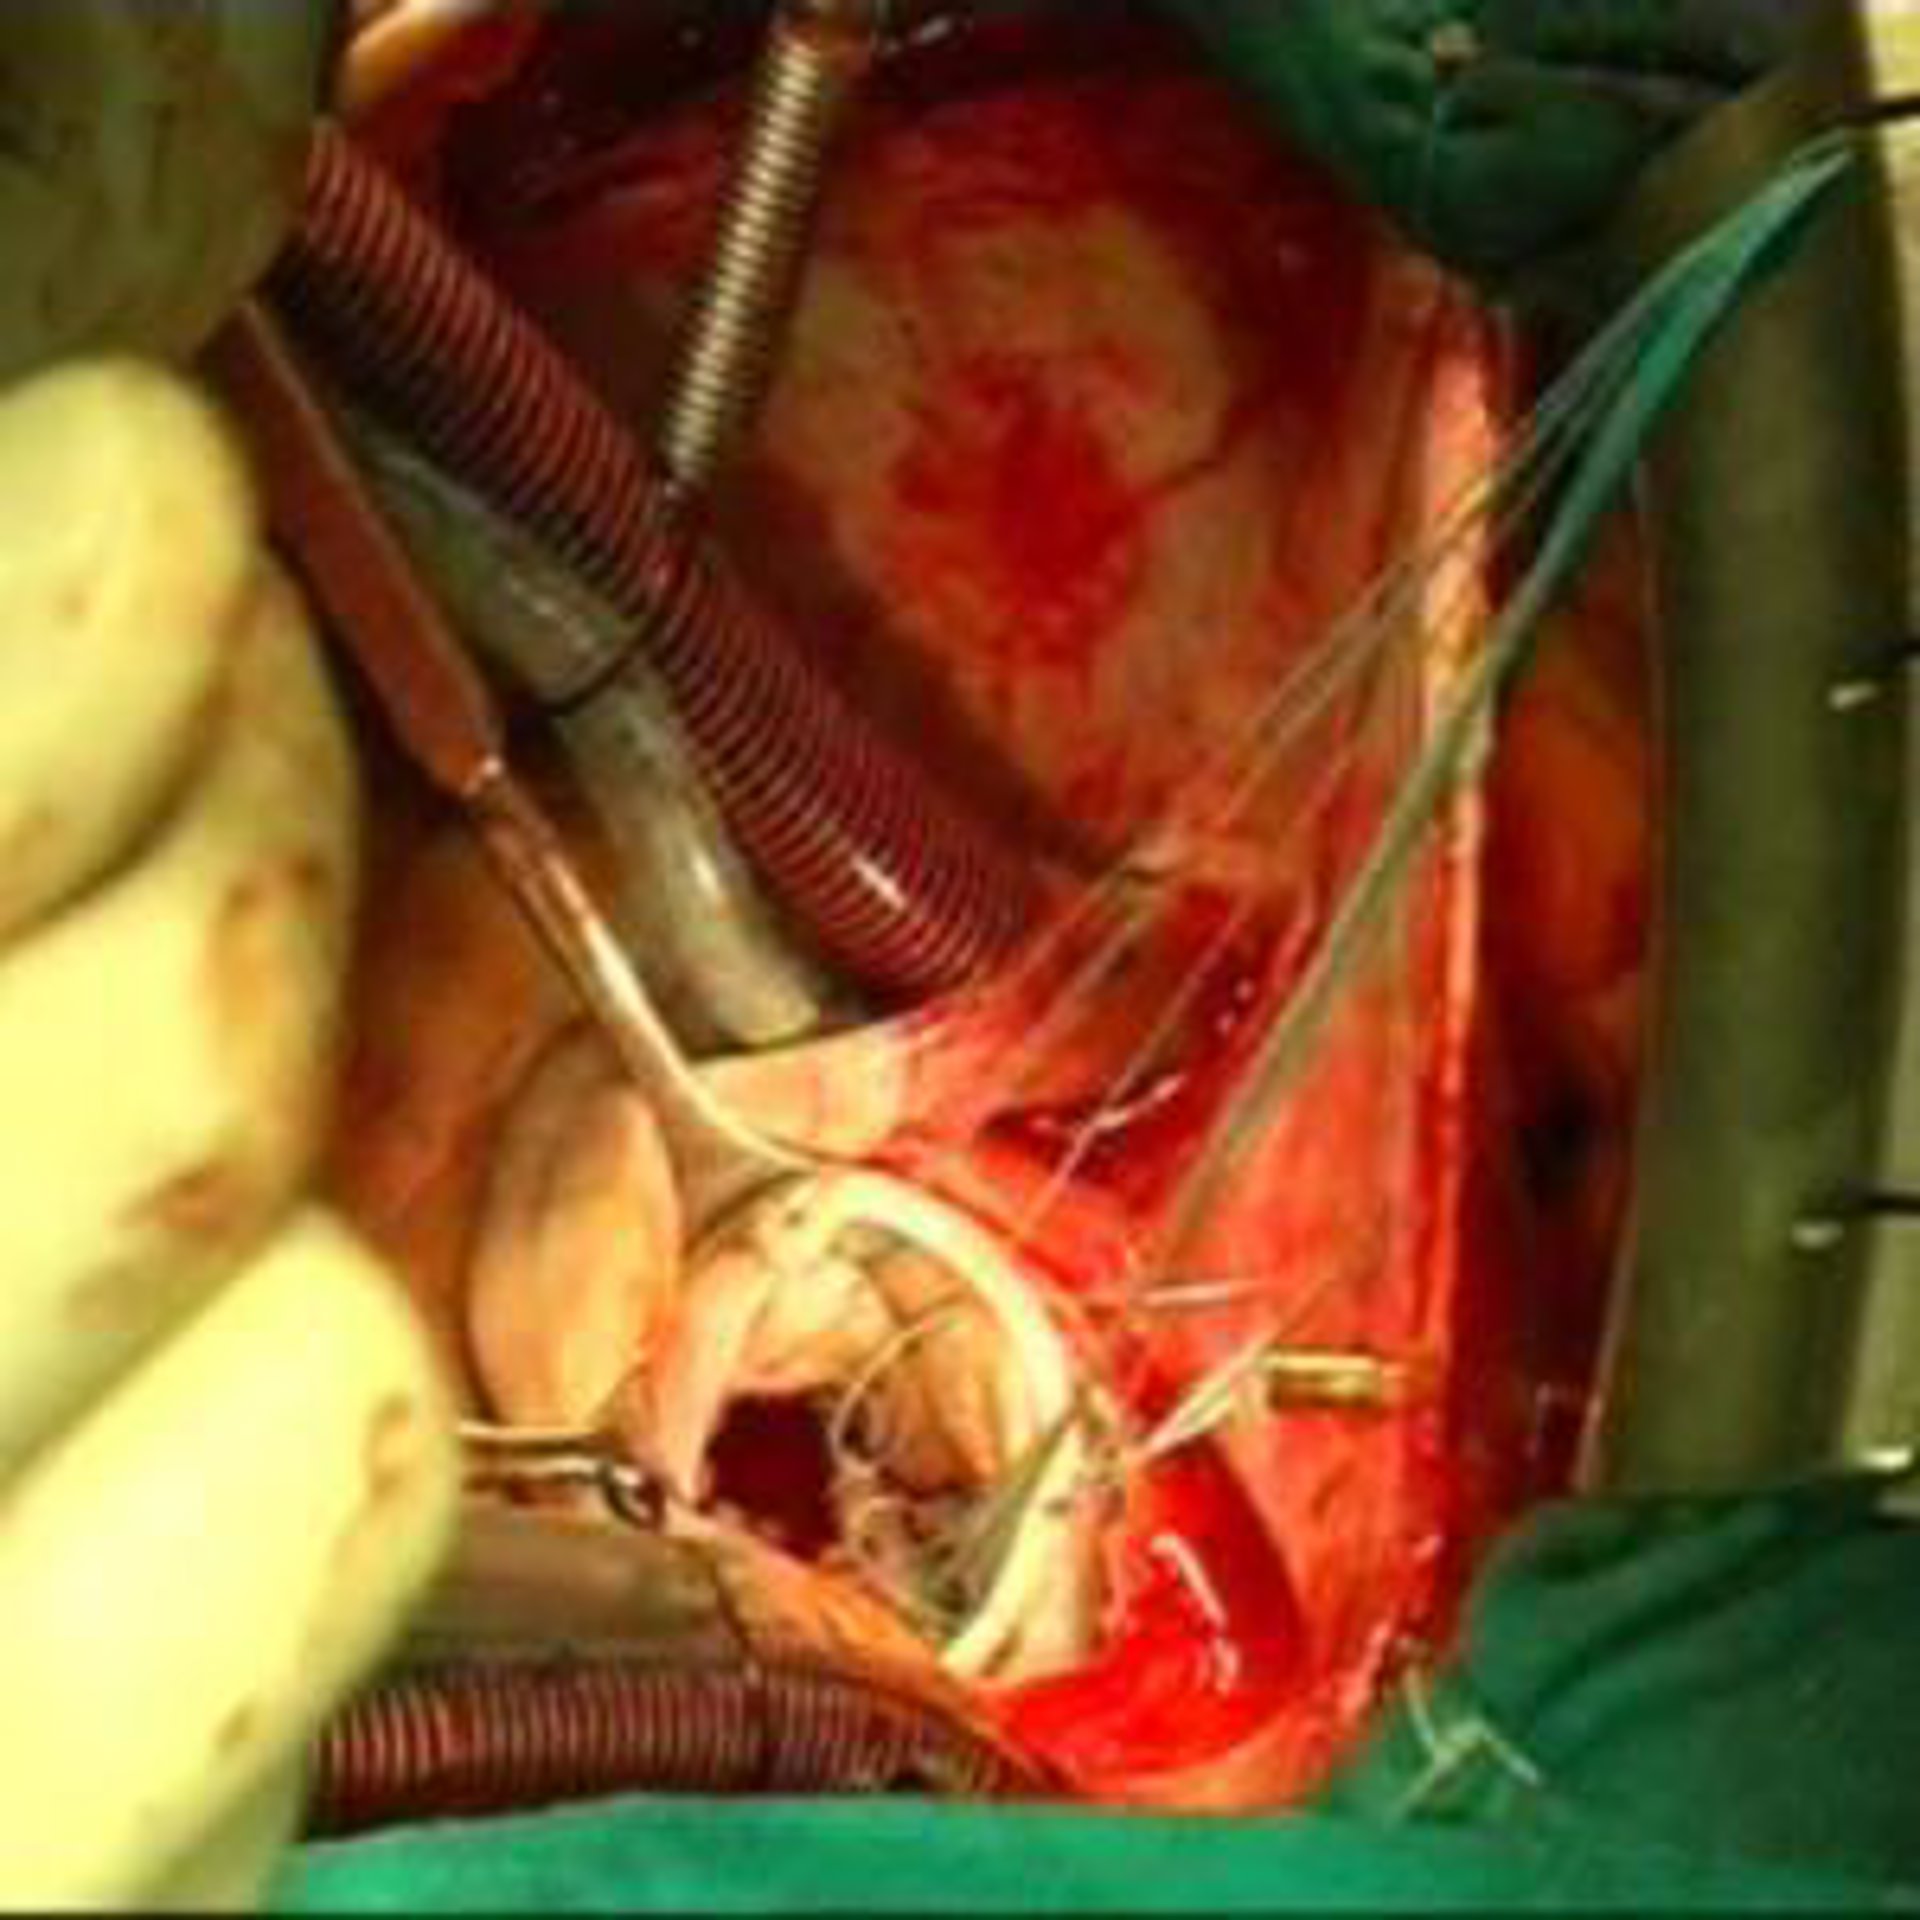

Añadió que tras la prueba endoscópica, que se realizó el pasado 30 de agosto y que duró apenas 10 minutos, la paciente permaneció 24 horas en Observación y monitorizada en la Unidad Coronaria, al objeto de controlar el comportamiento del corazón. Posteriormente, en concreto el 28 de septiembre, la paciente fue operada "mediante una cirugía rutinaria que no duró más de 45 minutos", prosiguió Infante.